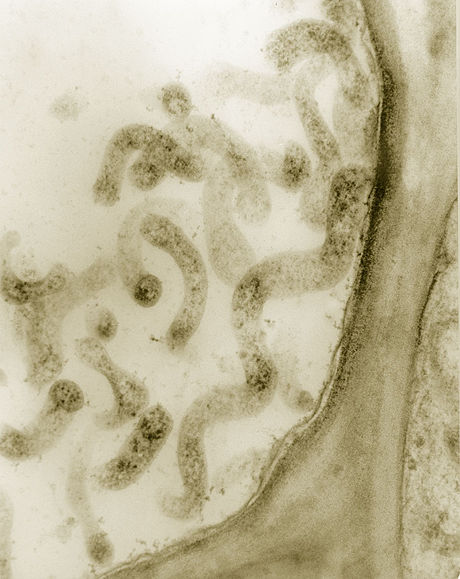

【マイコプラズマ】wikipedia